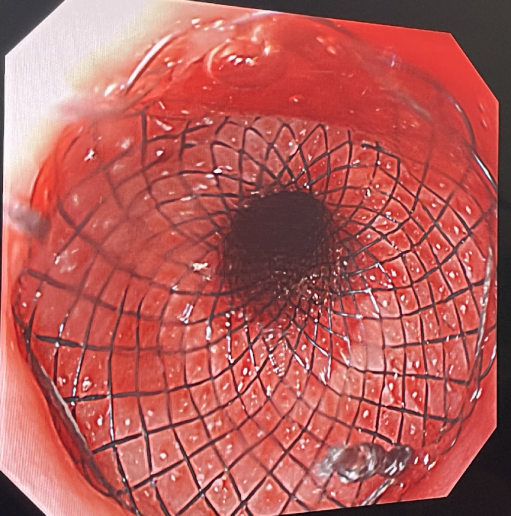

莫绪明教授和范志宁教授的MDT手术团队第一次讨论决定,小智的情况可以采用比“磁石压榨”技术创伤更小的穿刺支架技术恢复食道的通畅。两周后,团队为小智进行了第二次手术。医生再次扩张食管下段并将胃镜置于下段盲袋中,经口胃镜则置于上段盲端。在造瘘口胃镜监视下经口胃镜置入黏膜穿刺针,于盲端穿刺进入下段食管,沿穿刺孔放入导丝,在完成球囊扩张后,置入了由该院自主研发定制的全覆膜支架进行支撑,至此手术顺利完成。

曾经“闭锁”的食道,经过手术的重建,达到了同龄孩子正常的食道空间。经过了与美食隔绝的10个月,小智终于可以摆脱肠道营养,享受经口进食的快乐。即将出院的小智给南京市儿童医院心胸外科送上了锦旗和感谢信,深情地对莫教授说“是南京,是莫爷爷及叔叔阿姨们给了我希望,给了我第二次生命。南京,我将永远感恩。”